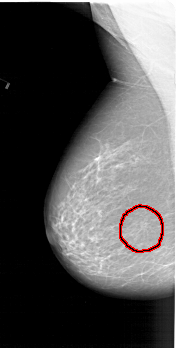

A_1410_1.RIGHT_CC

RIGHT_CC LINES 5716 PIXELS_PER_LINE 3256 BITS_PER_PIXEL 12 RESOLUTION 43.5 NON_OVERLAY

FILE: A_1410_1.LEFT_CC.OVERLAY

TOTAL_ABNORMALITIES 1

ABNORMALITY 1

LESION_TYPE MASS SHAPE ARCHITECTURAL_DISTORTION MARGINS ILL_DEFINED

ASSESSMENT 4

SUBTLETY 2

PATHOLOGY BENIGN

TOTAL_OUTLINES 1

BOUNDARY